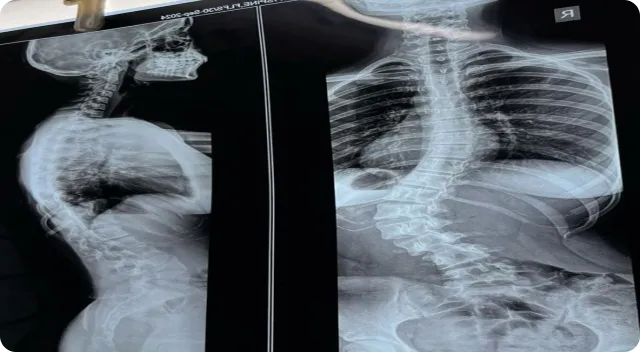

Introduction to Spinal Cord Injury

Spinal cord injury (SCI) is a neurological condition that occurs when damage to the spinal cord influences communication between the brain and different parts of the body. The functional impact varies depending on the injury level, severity, and individual health factors, often affecting mobility, sensation, or coordination. Long-term management commonly includes structured rehabilitation programs, physiotherapy, and assistive support strategies.

A spinal cord injury can result from trauma, compression, or medical conditions affecting spinal tissues. Depending on the injury location, individuals may experience variations in movement, muscle strength, sensory perception, or autonomic function. Because every injury profile is unique, multidisciplinary care involving neurologists, rehabilitation specialists, and physiotherapists is typically recommended to support long-term functional goals.